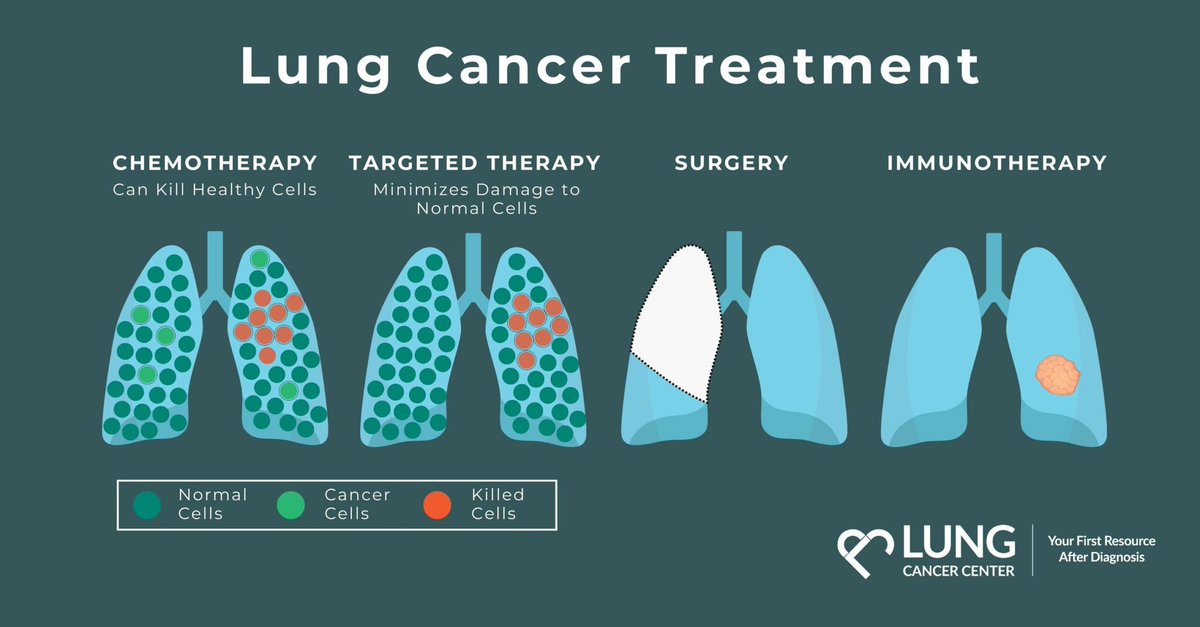

طرق العلاج

🏥 ثورة طبية في علاج سرطان الرئة:

• الجراحة التقليدية

• العلاج الكيميائي

• العلاج المناعي

• الطب الجيني الدقيق

المستقبل واعد! 💡 x.com

🏥 ثورة طبية في علاج سرطان الرئة:

• الجراحة التقليدية

• العلاج الكيميائي

• العلاج المناعي

• الطب الجيني الدقيق

المستقبل واعد! 💡 x.com